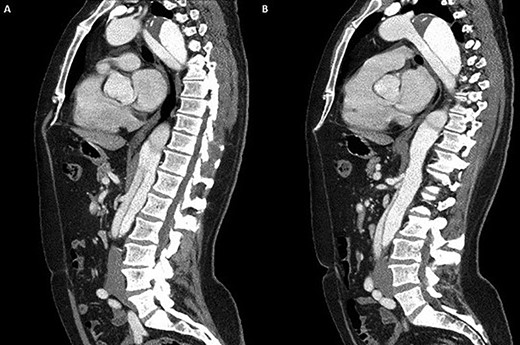

(A) Coronal section demonstrating the distal arch with the left vertebral and subclavian arteries visible; (B) coronal section demonstrating aneurysmal enlargement of the descending thoracic aorta and Type B dissection.

A 52-year-old gentleman presented to our institution with a previous history of TBAD (diagnosed 3 years previously), which was managed conservatively. His comorbidities included hypertension and excision of a left frontal cavernoma with no family history of aortic aneurysm or dissection. Following his initial presentation of chest pain, the patient had remained asymptomatic and stable. Surveillance management was initially instituted and the case discussed at the aortic multidisciplinary meeting. Due to retrograde extension of the TBAD into the distal arch, persistence of the false lumen, increasing descending aortic dimensions (6.0 cm) and an anomalous left vertebral artery originating from the aortic arch, the patient proceeded to aortic arch surgery and antegrade deployment of the stent into the descending aorta with a FET graft (Figs 1, 2). Preoperative coronary angiography and transoesophageal echocardiography revealed no coronary artery disease and a competent trileaflet aortic valve with preserved left ventricular function.